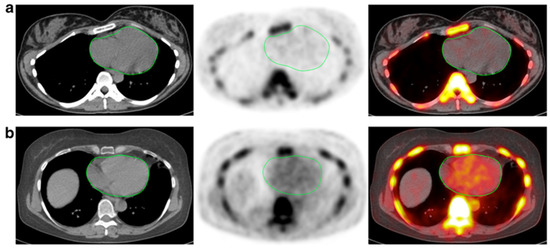

Figure 5.

FDG-PET images of a 78-year-old woman with giant cell arteritis at the baseline (a), 3 months of therapy (b), and 6 months of therapy (c). High-tracer uptake is initially present and visible in the thoracic aorta and subclavian arteries, as evident in the first two images from the left (a), which progressively decreased after treatment with steroids (from Blockmans et al. [142] with permission).